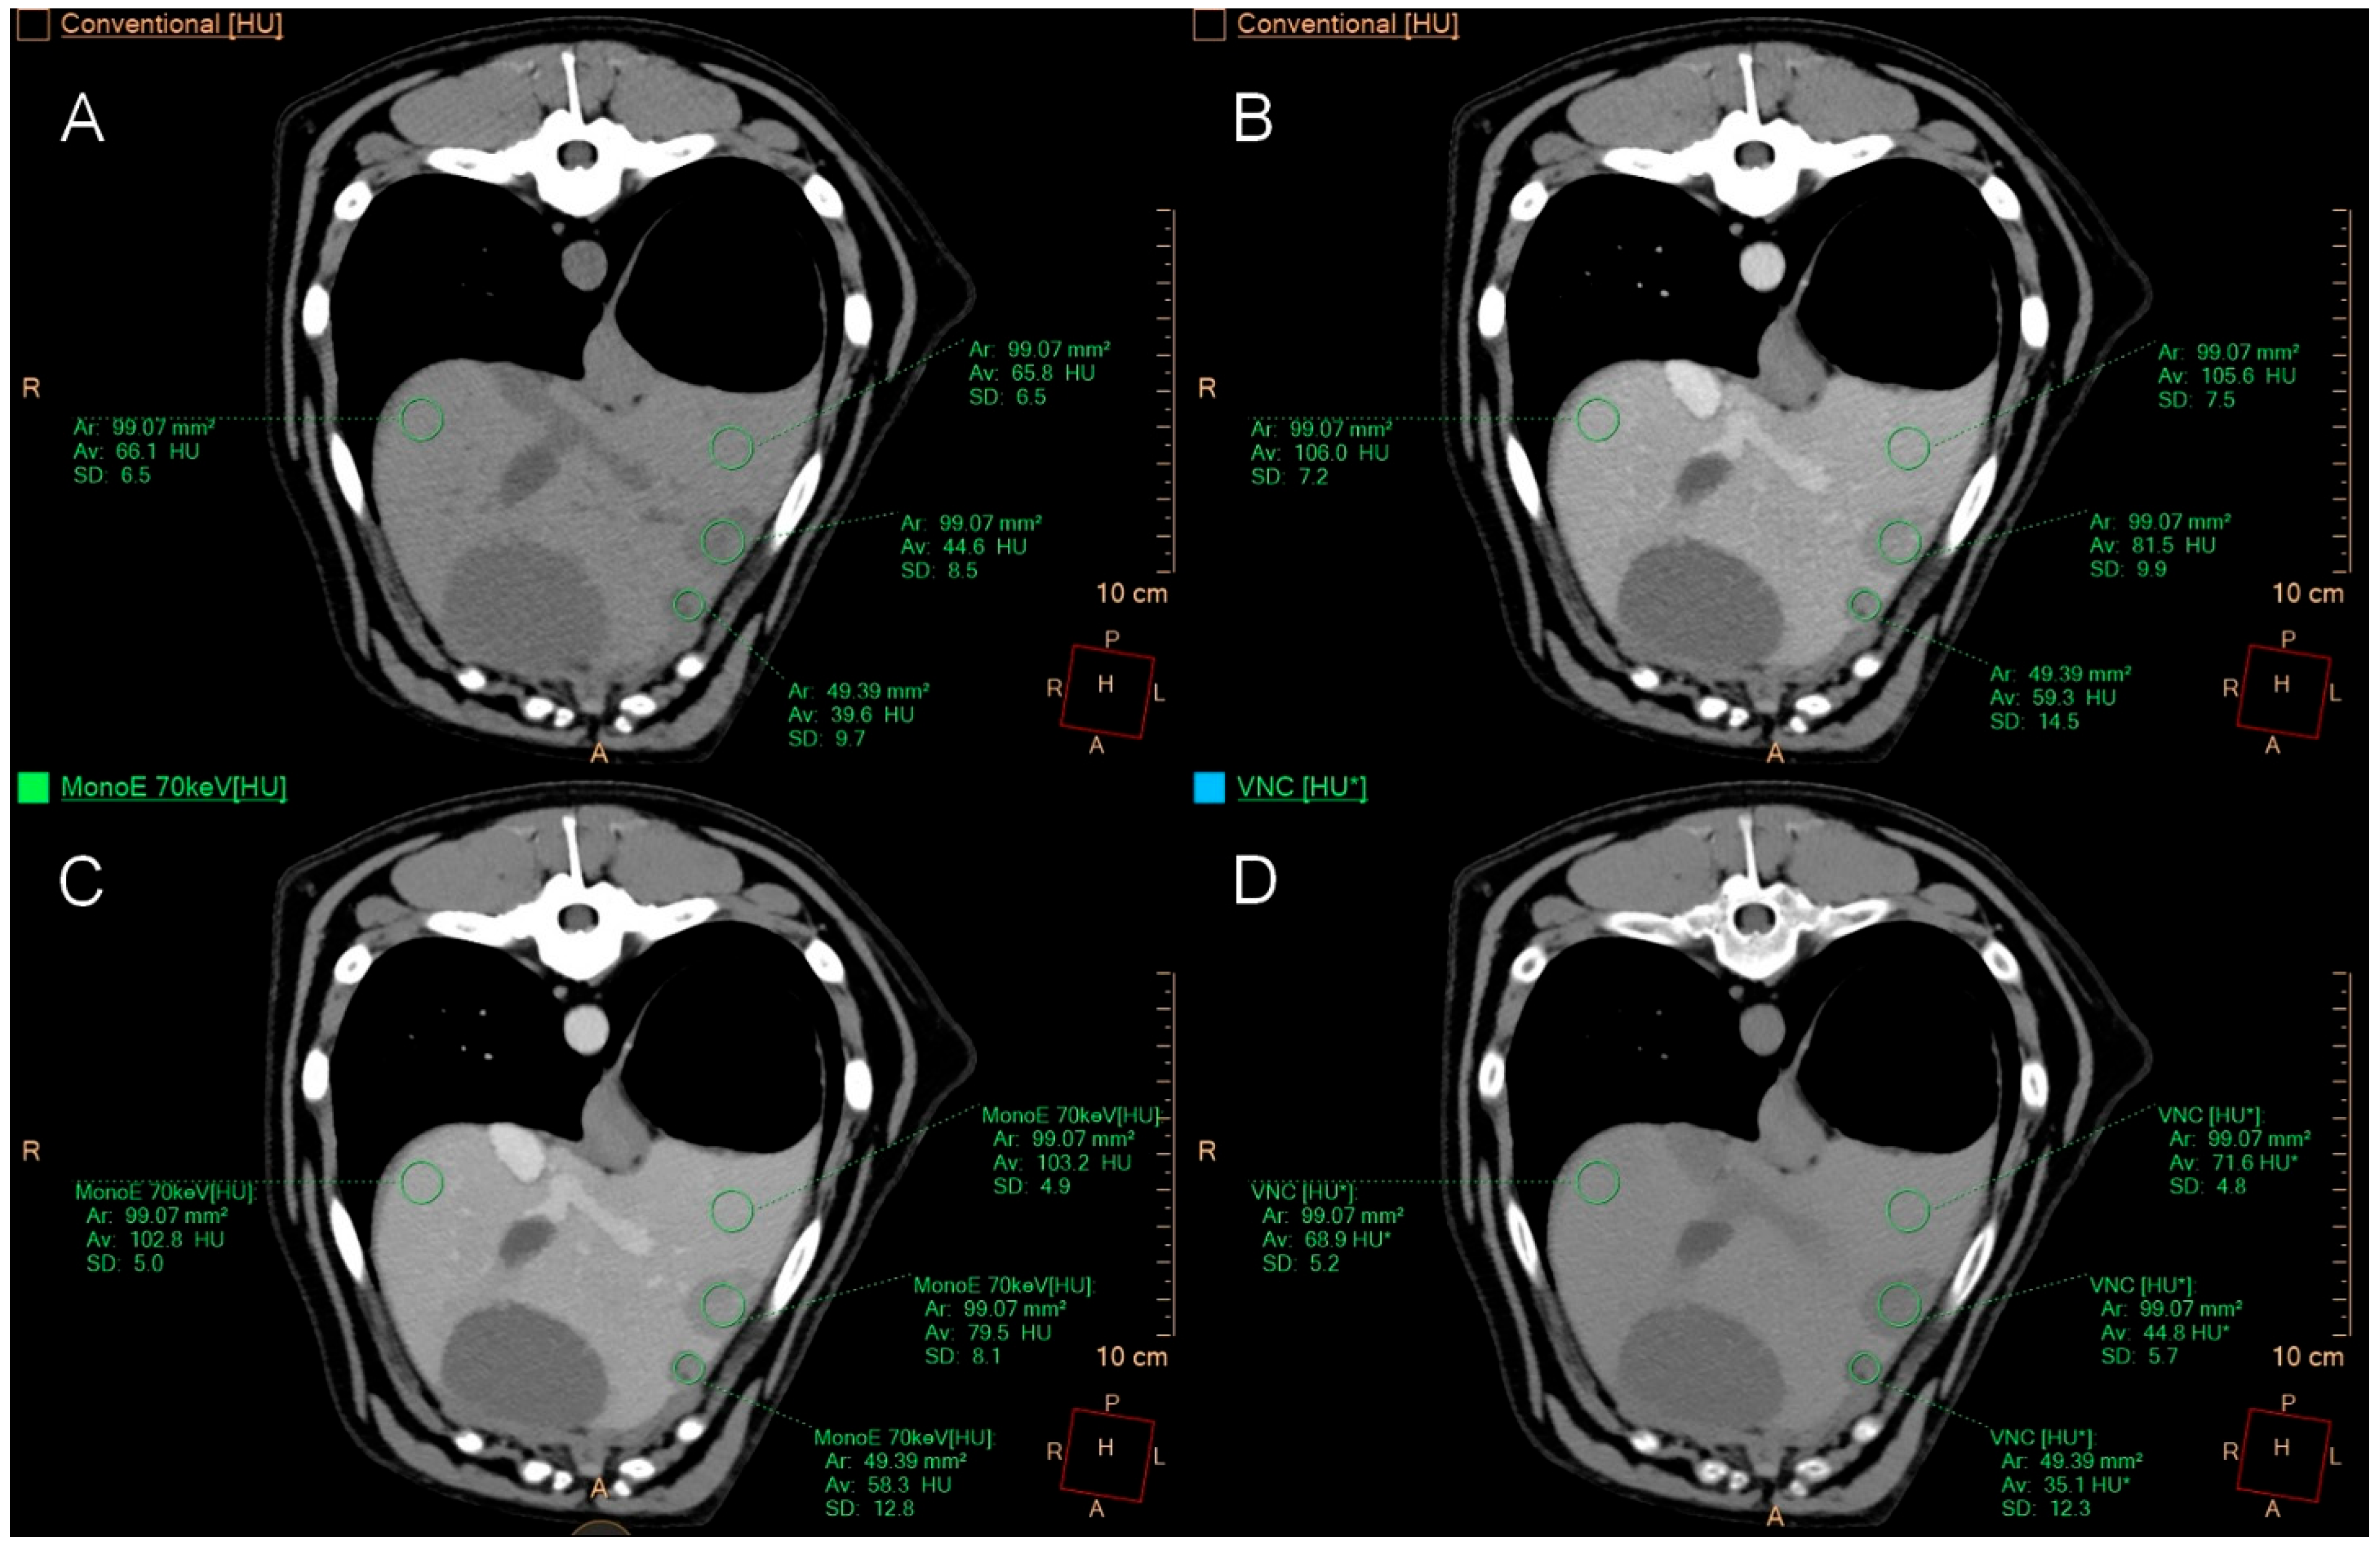

2.4. Quantitative Image Analysis

3.4. Quantitative Image Analysis